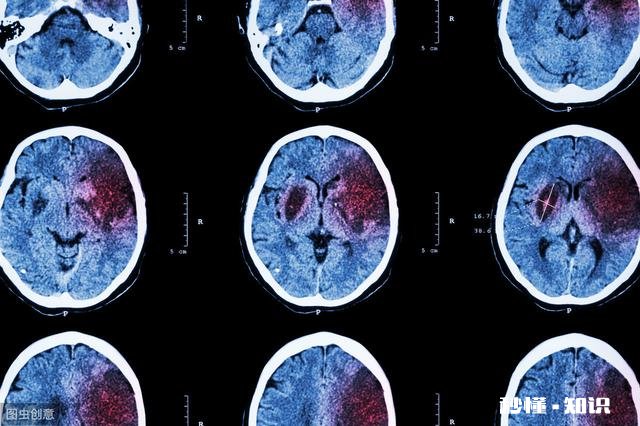

个别轻度脑出血病人临床症状轻,与脑梗死相似,两者难以鉴别 。而大面积脑梗死病人,出现颅内压增高,意识障碍时,也酷似脑出血,临床上不好区分 。要力争尽早做CT扫描检查 。

文章插图

脑出血的CT表现为高密度阴影,而脑梗死表现为低密度阴影,两者截然不同 。